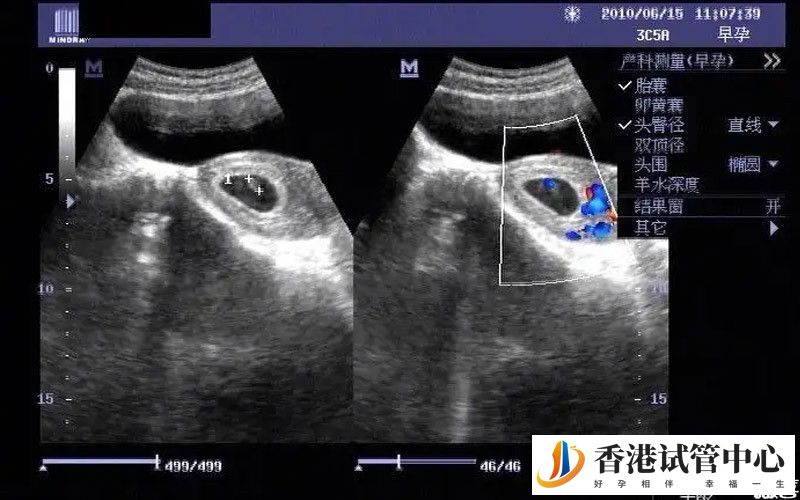

卵黃囊對于懷孕后的女性來說是非常重要的,尤其是懷孕初期如果沒有卵黃囊,或者卵黃囊指標不在正常值范圍,那么胎停的風險就特別大,因此孕初期的準媽媽們若是自己長時間看不到卵黃囊,或者卵黃囊的大小、直徑不正常,那么就必須要引起重視,及時采取有效的解決措施。

孕婦卵黃囊的正常范圍為3-8mm,大小隨著孕周而變化,在妊娠5周開始出現,在孕10周左右達到最大直徑,一般不會超過8mm,若卵黃囊直徑大于6.1mm,提示發育異常,若直徑大于7mm,胎停的可能性會比較大,當直徑8mm,基本可以可以判定為胎停育。

卵黃囊的大小不僅可以用來診斷胎停育,而且還可以用來測宮外孕,若孕期出現卵黃囊,那么可以肯定為宮內懷孕,并且胚胎是存在的,但若是沒有發現卵黃囊,或者卵黃囊小于正常值范圍至今,那么很可能是宮外孕,這個時候需要進一步檢查,若確診需終止妊娠。

另外,在孕早期若未見胎心搏動,但卵黃囊大小正常也很清晰,那么可以確定的是胚胎良好,而若卵黃囊直徑大小大于10mm,就可能預示胚胎發育不良,當妊娠囊大于20mm卻未見到卵黃囊或者胚胎的時候,那么不排除是孕卵枯萎,屬于難免流產。

孕婦的卵黃囊正常情況下從孕5周開始出現,孕12周以后縮小直至消失,大部分女性在懷孕6周左右就需要通過b超檢查看宮腔內有無卵黃囊,以及卵黃囊的直徑大小,確定卵黃囊是否在正常值范圍內,若發現異常現象,須在相關醫生的指導下采取有效的處理手段。